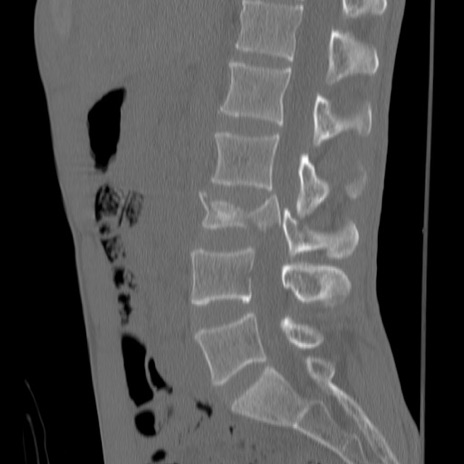

症例3 腰椎CT(矢状断像)

腰椎CT

冠状断像